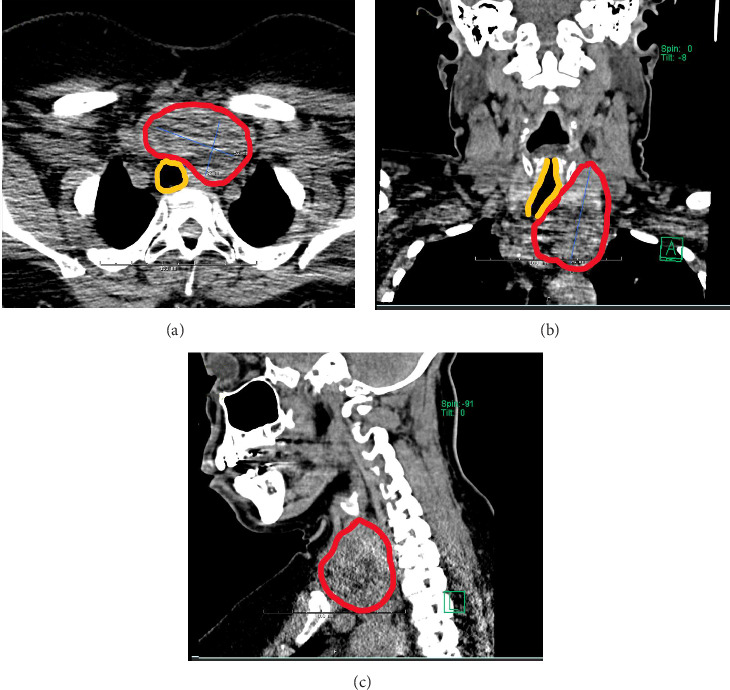

Background: Obstructive sleep apnea (OSA) and nontoxic multinodular goiter are conditions that often coexist. Treatments of both conditions have evolved over time, but continuous positive airway pressure (CPAP), oral appliances, or surgical therapy are often needed. Radiofrequency ablation (RFA) of the soft palate and base of tongue has been applied as a newer alternative therapy for OSA. RFA is also an increasingly used approach for thyroid nodules and goiter, but previously had no known connection to OSA. Case Presentation: A 59-year-old female with a known history of multinodular goiter and moderate OSA was referred to our endocrine surgery clinic. The goiter was found to have mediastinal extension, documented longitudinal growth of the dominant nodule, cosmetic deformity of the neck, and tracheal deviation. The patient underwent thyroid RFA as nonoperative treatment for her goiter. Within a month of her procedure, she also self-reported a subjective reduction in apneic events and later underwent a formal home sleep study demonstrating an apnea-hypopnea index (AHI) change from 15.8/h at diagnosis to 2.9/h currently, signifying resolution of her OSA. Her treated nodule had 92% volume reduction on 18-month follow-up visit. Conclusion: To our knowledge, this is the first reported case of OSA cured in a patient undergoing RFA for goiter. Goiter-associated sleep apnea remains inadequately described in the literature and warrants further investigations on prevalence and management. Thyroidectomy continues to be the definitive treatment for goiter, with some studies suggesting secondary efficacy for OSA. RFA is now established as a first-line option for symptomatic thyroid nodules, but previously had no described benefit to OSA symptoms. This report illustrates that RFA of thyroid nodules could be offered to patients as both an effective nonsurgical option for goiter as well as a potential cure for their OSA to free them from nightly CPAP usage.

Abstract Image